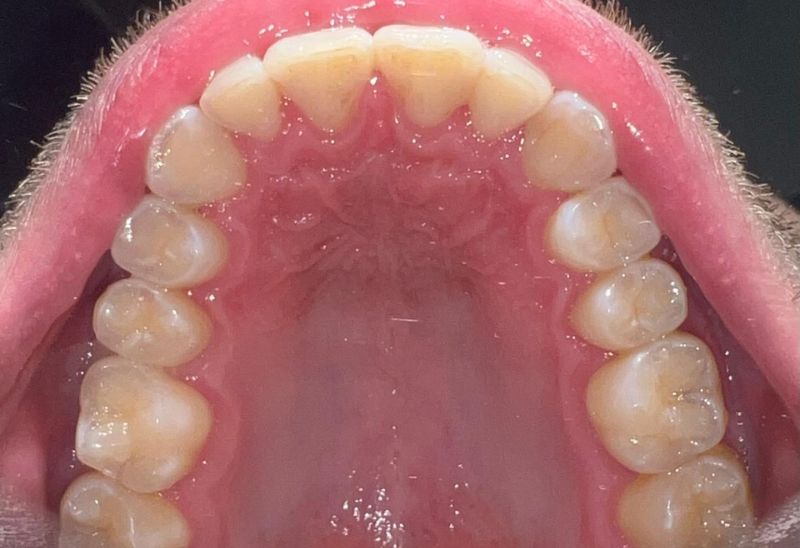

Prima e dopo l'apparecchio invisibile

In questa sezione mostreremo risultati reali ottenuti con l’ortodonzia invisibile a Roma. I cambiamenti riguardano non solo i denti, ma anche l’armonia del viso, la postura orale e l’autostima.